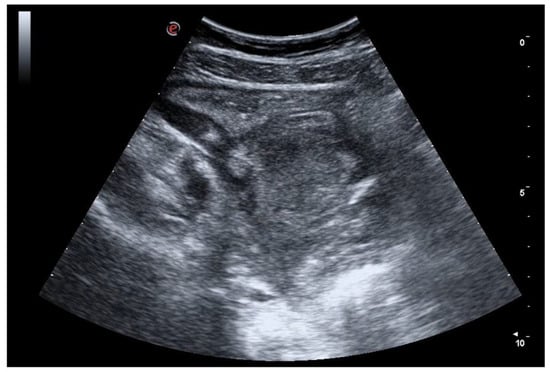

6. Bowel Obstruction